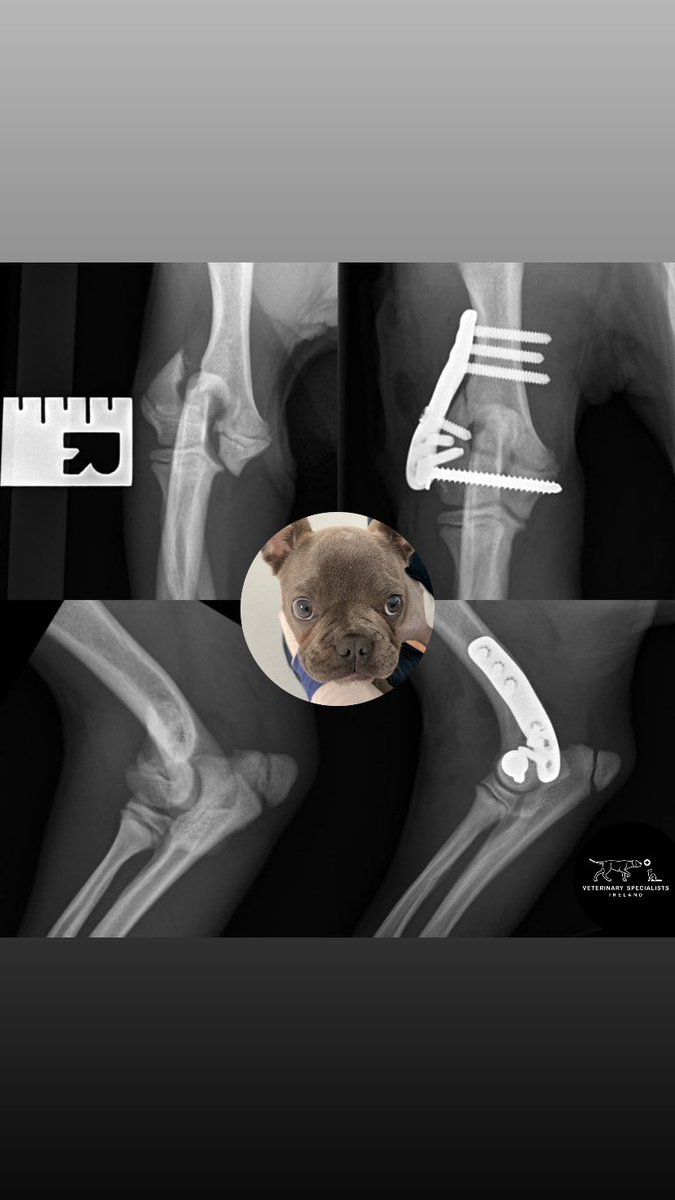

Did you know that baby Frenchies are particularly prone to elbow fractures? Early and accurate repair is essential to restore and maintain a healthy elbow joint 💪🏻 We use custom 3D-printed implants designed specifically for French Bulldogs to optimise repair #mischiefmanaged

Did you know that baby Frenchies are particularly prone to elbow fractures?

Early and accurate repair is essential to restore and maintain a healthy elbow joint 💪🏻

We use custom 3D-printed implants designed specifically for French Bulldogs to optimise repair

Ready to move on from 2020, Bluebell is now sporting the very nifty French Bulldog LEAP from Fusion Implants. Nice to save time on a difficult fracture late on NYE! Contact Fusion about implants and training. @CGVetSpecialist #vetortho

Ready to move on from 2020, Bluebell is now sporting the very nifty French Bulldog LEAP from <a href="/FusionImplants/">Fusion Implants</a>. Nice to save time on a difficult fracture late on NYE! Contact Fusion about implants and training. @CGVetSpecialist #vetortho